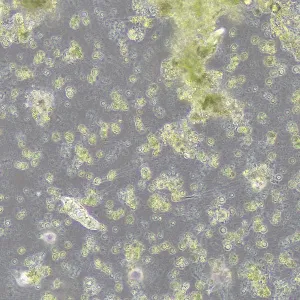

Фазово-контрастная микроскопия позволяет увидеть детали прозрачных образцов, которые практически не видны в светлом поле, и при этом не повреждать их окрашиванием. Метод применяют в разных сферах: медицине, биологии, ветеринарии, сельском хозяйстве, фармацевтике, экологии.